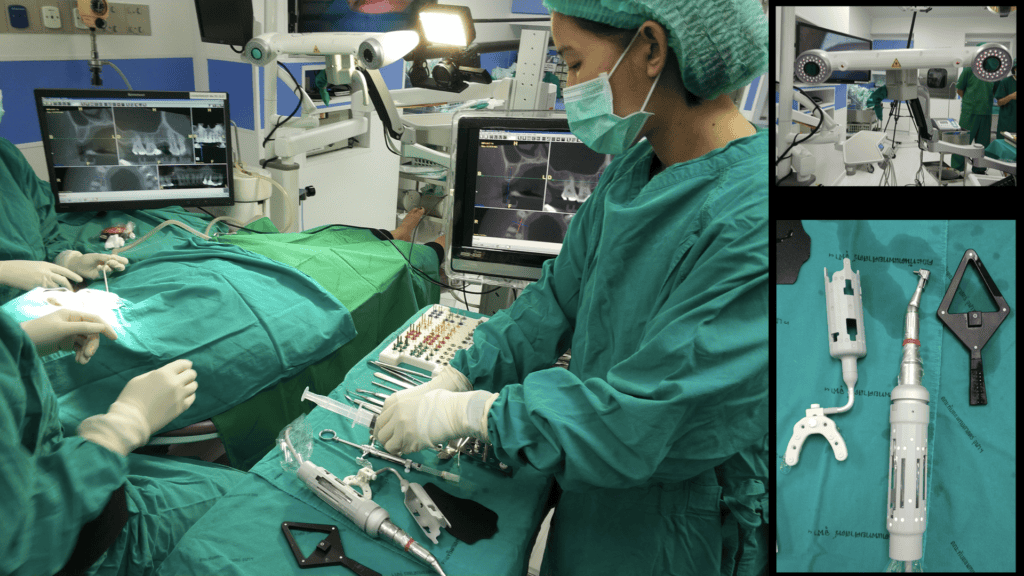

The dynamic CAIS systems are based on a principle which reminds the GPS navigation. In the first generation systems, a set of stereoscopic cameras was constantly recording the position of a set of trackers (called fiducial markers) on the patient and the surgeons handpiece. The software then calculated the exact location of the patient and the handpiece in space and projected the drills on the actual patient’s CBCT in real time, through a screen (Figure 3). Of course, this only made sense if the software could maintain at all times a proper spatial alignment of the patient and the drills. To achieve this, the patient had to wear a custom-made split during the CBCT and during surgery, but also sensitive registration and calibration procedures were required before the surgery. The first and second generation of dynamic systems utilised many components and required rather big areas of fiducial markers (Figure 3). Like in static CAIS also here, there is not a uniform technology and many companies have developed different systems. In this way, there has been systems with 2, 3 or 4 tracking cameras, different size and design of fiducial markers and calibration procedures, as well as different planning and visualization software. There is very little reported in research with regards to comparisons on different dynamic CAIS systems, so one can only try to assess systems performance based on their reported specifications.

The third generation of navigation systems has reduced the need of an intraoperative splint for the patient and instead aligns the surgical visualization via an algorithm directly with the CBCT, using distinct anatomical landmarks on teeth. In general, the trend has been to reduce the number of components as well as streamline the design to smaller and easier to use. One of the latest developments is the addition of augmented reality glasses, which has made the need for chairside operating monitor redundant. This is a major improvement for both speed and ergonomics, as the surgeon has now the navigation screen projected in the upper segment of his view and can perform the surgery without interrupting optical contact with the surgical field. Combining the augmented reality glasses however with surgical loops and light might be a challenge. Learning to operate with all these gadgets mounted and a 3-layer field of vision would require some learning and adaptation (Figure 4).